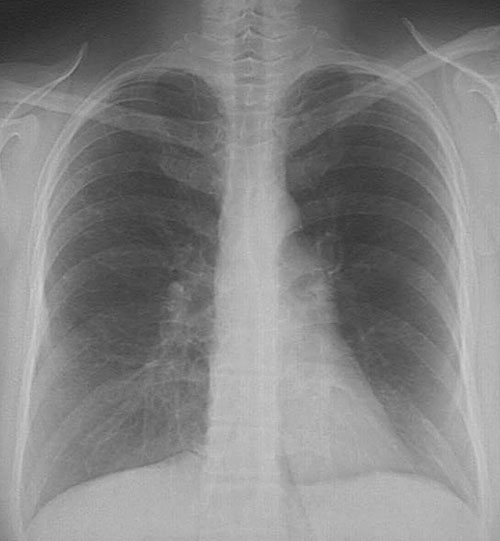

The chest radiograph shown here demonstrates a reticular pattern, mainly in the upper lobes, that has resulted from progressive pulmonary fibrosis and early honeycomb change.